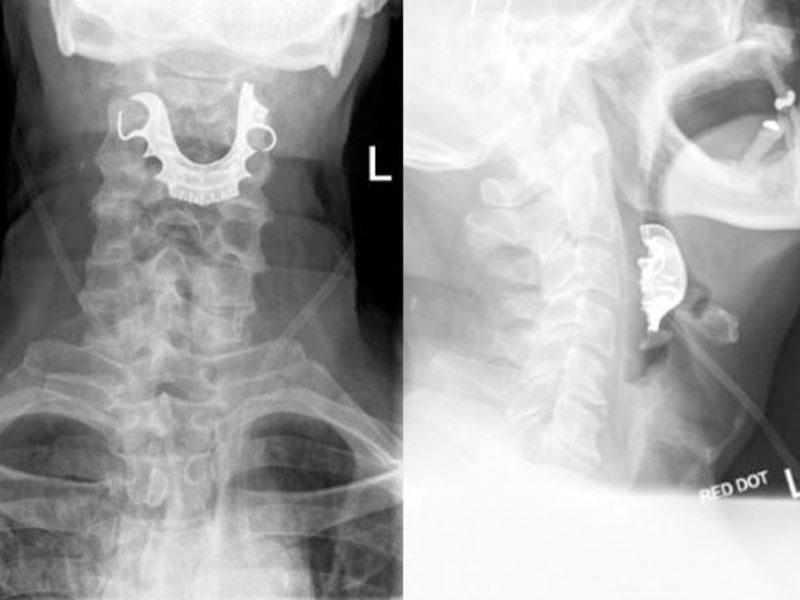

7News.Az axşam.az-a istinadən bildirir ki, 72 yaşlı xəstə qarın nahiyəsində aparılan əməliyyatdan 8 gün sonra udquna bilməmək və öskürək şikayətləri ilə həkimə müraciət edib. Rentgen müayinəsi aparılan zaman isə ortaya çıxan görüntü həkimləri şoka salıb.

Belə ki, əməliyyat zamanı xəstənin ağzında olan protez dişlər onun boğazına düşüb. Bu hadisə tibb dünyasını ayağa qaldırıb. Mütəxəssislər baş verənlərin həkim səhlənkarlığı olaraq dəyərləndiriblər. Protez dişləri olan insanlar narkoz verilən zaman onların dişləri çıxarılmalıdır. 72 yaşlı ingilisin dişini çıxarmaq isə heç kimin ağlına gəlməyib.